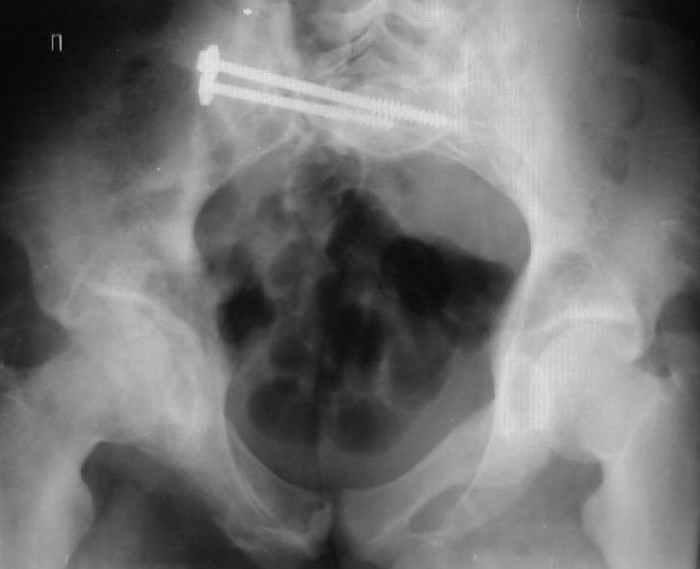

Re: Застарелый перелом таза

Для информации к размышлению о возможности исправления имеющейся деформации предлагаю похожий случай.